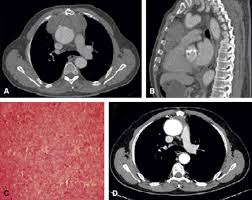

Solitary Fibrous Mediastinal Tumor With Coronary Vascular Supply An Unusual Case The Journal Of Thoracic And Cardiovascular Surgery

Solitary Fibrous Mediastinal Tumor With Coronary Vascular Supply An Unusual Case The Journal Of Thoracic And Cardiovascular Surgery from els-jbs-prod-cdn.jbs.elsevierhealth.com